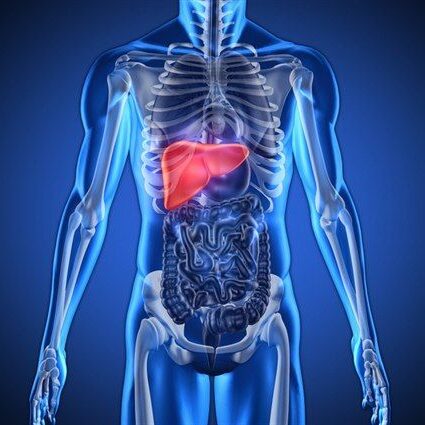

Trávení a funkce jater

BICOM - Biorezonance upravuje a podporuje správnou funkci trávicího traktu a jater, které hrají klíčovou roli v metabolismu tuků i v celkové detoxikaci.